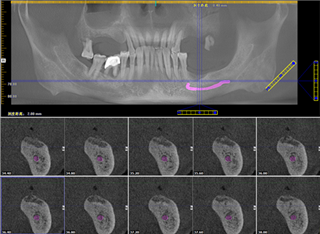

郭老牙齿全景片